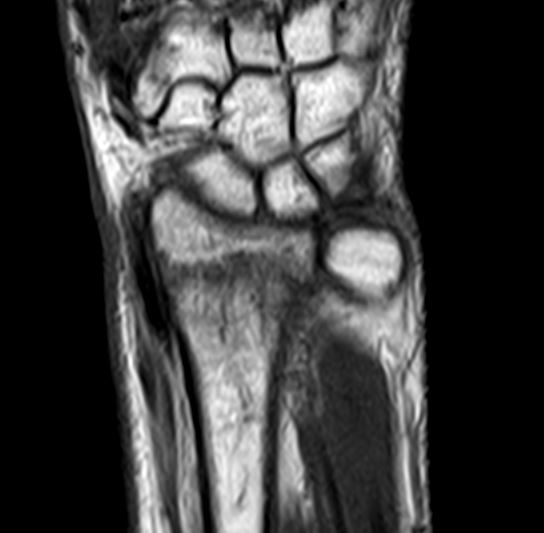

念のためにMRIを撮像すると、やはり橈骨遠位端骨折のようです。圧痛点も関節ではなく、橈骨遠位端なので、画像と身体所見が一致しました。